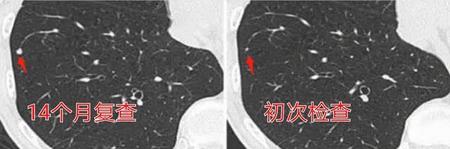

上图这位老爷子,体检发现右下肺2毫米微结节,14个月后复查结节增大,23个月的时候接近一厘米,进行了胸腔镜手术切除,病理竟然是小细胞肺癌。